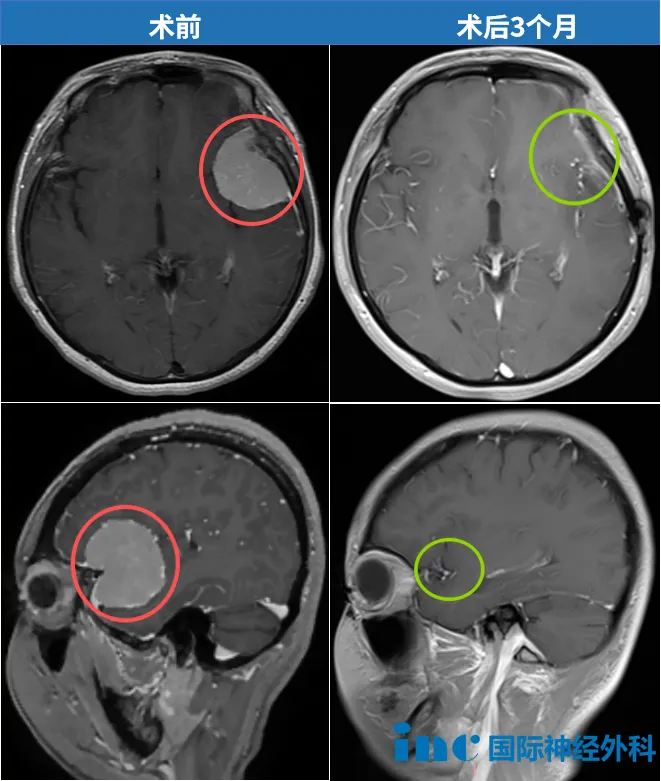

"病灶现已完全消失。影像学检查显示无肿瘤残留或复发迹象,所有指标均符合预期,患者目前无需任何辅助治疗。"

开颅手术后三个月,我收到INC巴特朗菲教授的术后随访报告。最令人振奋的是,教授在报告上亲笔书写了四个中文汉字:"不能更好"。这一刻我确信,这场与脑膜瘤的战役已取得胜利。作为38岁的企业经营者,我始终将自身视为"生命的掌舵者"。正如商业运营需要战略视野,面对疾病更需要全局思维。从体检意外发现脑膜瘤开始,我就在观察与治疗、放疗与手术、早期干预与延期处理等选项中,系统规划最佳治疗方案。

"言语功能完全正常,肢体活动无碍,精神状态远超预期!"当巴特朗菲教授亲自查房确认肿瘤全切时,我激动不已——这是人生中最正确的决定。考虑到美观需求,巴教授仅剃除切口周围1厘米头发。术后第7天,我顺利出院。